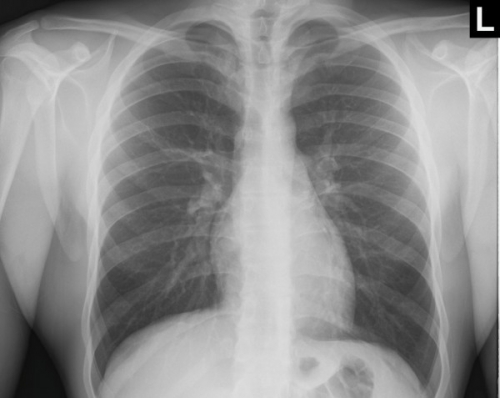

Tool to train medical student's eyes as to what a normal chest x-ray looks like, with over 500 consecutive normal images.